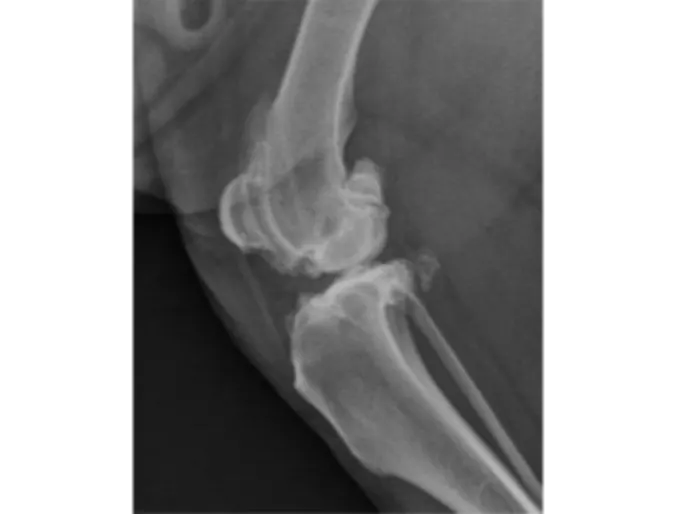

Figure 2. Radiograph of a canine stifle (knee joint) with advanced arthritis. Same dog as in figure 1, opposite stifle.